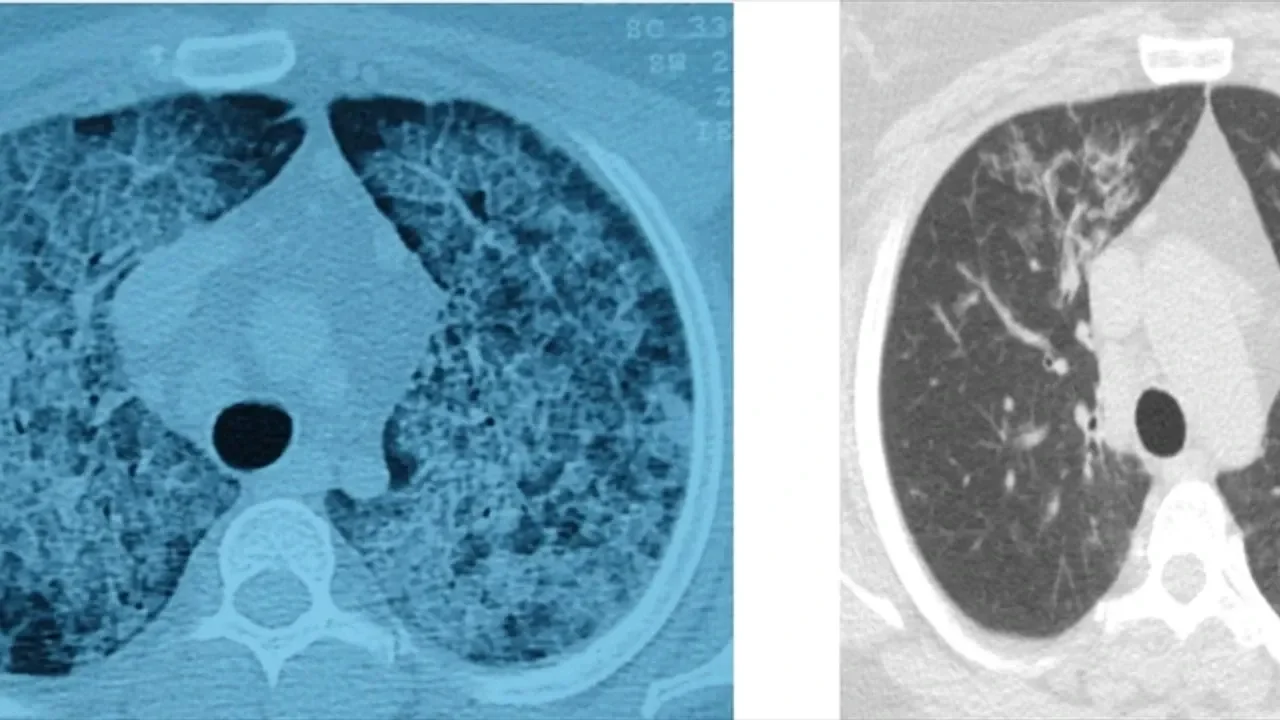

Hastalığın, kişinin kendi yağ ve proteinlerinin temizlenmesiyle görevli hücrelerdeki sorun nedeniyle akciğerlerdeki hava keseciklerinin birikmesi sonucu ortaya çıktığını aktaran Ergur, belirtilerin nefes darlığı, yorgunluk ve aşırı halsizlik olduğunu kaydetti.

Ergur, hastalığın çoğu zaman astımla karıştırıldığını, tanının ancak ileri tetkiklerle konulabildiğini ifade etti.